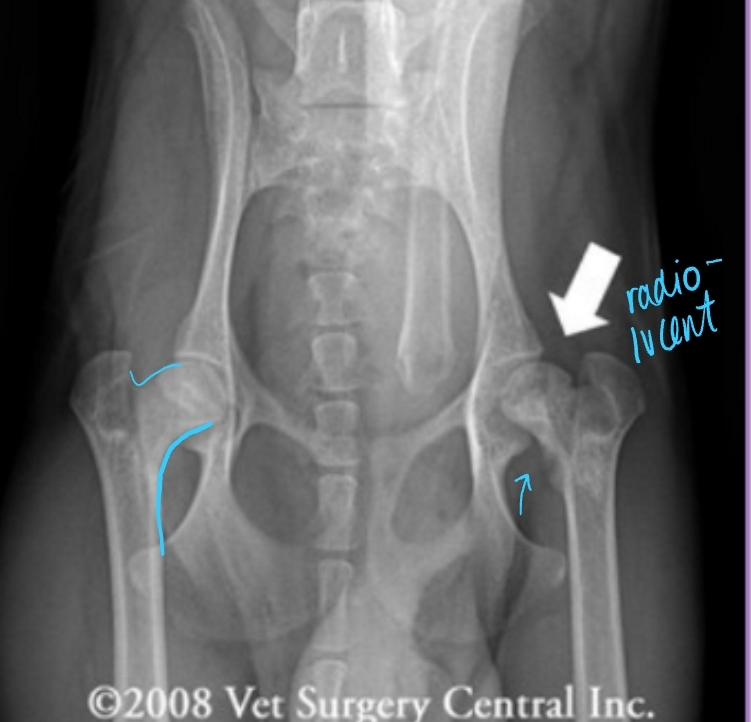

Hip Luxation Pathophysiology

Et: Results from failure or tear of Joint capsule or Round ligament

Most common joint luxation in dogs

Types:

Craniodorsal (#1): hit-by-car or blunt trauma

Caudoventral: fall with abduction

Hip Luxation Diagnosis

Cs: Crepitus, pain, shortened limb length(craniodorsal), pelvic asymmetry

Palpate: Iliac crest(wing), Greater trochanter of femur, and Ischiatic tuberosity form a straight line

Normal = shallow triangle

Thumb test: Place thumb in ischiatic notch and externally rotate limb

Normal = Thumb should be pushed out of notch

Radiographs: lateral & VD